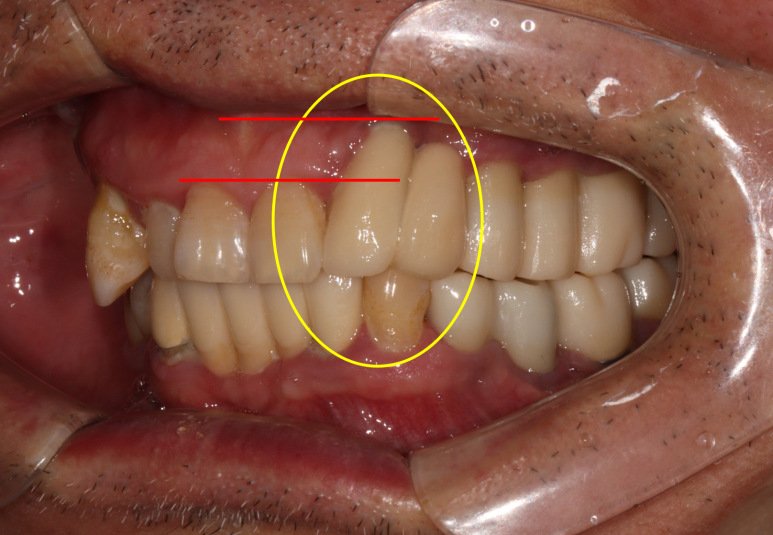

저희 병원에 오셨던 60대 남자 환자분입니다.

딱 봐도 구강위생상태가 좋지 않습니다...

잘 보시면 적절히 관리되지 않아 다수 축적되어있는 치태와 치석들을 쉽게 보실 수 있죠.

아~ 잇몸이 좋지 않았습니다. 그래서 스케일링과 잇몸치료 그리고 필요한 치아를 뽑고 임플란트 하기를 권해드렸죠. 이 분이 3년만에 저희 병원에 다시 오셨는데요.

오른쪽 위 송곳니가 잇몸이 붓고 흔들려서 뽑고싶어요.

이번에 저희 치과로 오신 이유는 바로 이 송곳니 때문이었습니다.

딱 봐도 만성 치주염이 너무 심해서 고름이 맺혀있는 것을 보실 수 있죠..

이미 병적 치아 이동 상태 (pathologic migration)이 심해서 치아는 내려오고 치아 사이 틈은 더 벌어진 상황.

속된말로 치아가 둥둥 떠있었습니다.

보시면 치아의 병적 이동으로 이미 자기 자리에서 한참 이탈해버린 오른쪽 위 송곳니를 보실 수 있습니다.